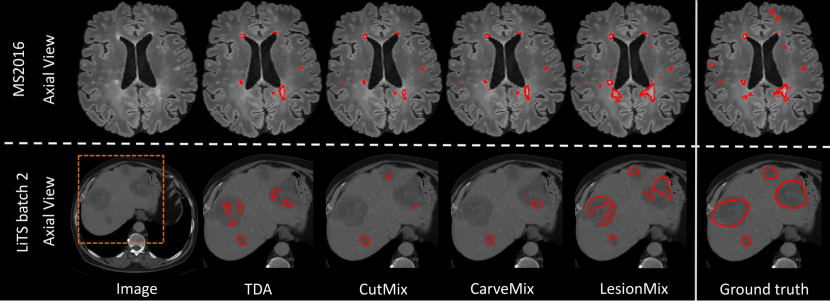

Following the ablation study, we choose the uniform lesion load distribution for the remaining experiments. We compare LesionMix to SOTA data augmentation methods, including traditional data augmentations (TDA), which come default with nnU-Net [12], CutMix [26] and CarveMix [28]. TDA includes rotation, scaling, mirroring, elastic deformation, intensity perturbation and simulation of low resolution. We add CutMix, CarveMix, or the proposed LesionMix onto TDA. We re-implement CutMix [26] for 3D medical images, and use the public code for CarveMix [28]. We are unable to compare against SelfMix [29] due to unavailability of public code. For fair comparison, all methods use nnU-net as the segmentation network and augment the WMH2017 training set for brain lesions and the LiTS batch 1 dataset for liver lesions by five times. We conduct experiments when different sizes of the training data is used. Table 4 reports the lesion segmentation Dice scores for different data augmentation methods. LesionMix improves lesion segmentation against SOTA methods in the majority of experiments. We notice greater statistical significance in experiments with smaller dataset sizes. We present example segmentations against benchmark methods in Figure 5.

Refer to caption

Figure 5: Qualitative comparison of segmentation performance when 10% of dataset size is used. Models with LesionMix detect more lesions and segment them more accurately.